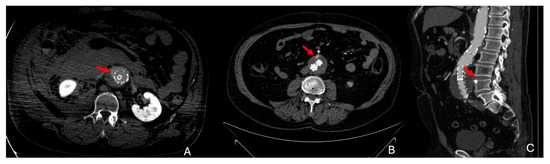

3. CTA Findings of Aneurysm Rupture

- Rakita, D.; Newatia, A.; Hines, J.J.; Siegel, D.N.; Friedman, B. Spectrum of CT Findings in Rupture and Impending Rupture of Abdominal Aortic Aneurysms. RadioGraphics 2007, 27, 497–507. [Google Scholar] [CrossRef]

- Schwartz, S.A.; Taljanovic, M.S.; Smyth, S.; O’Brien, M.J.; Rogers, L.F. CT Findings of Rupture, Impending Rupture, and Contained Rupture of Abdominal Aortic Aneurysms. Am. J. Roentgenol. 2007, 188, W57–W62. [Google Scholar] [CrossRef]